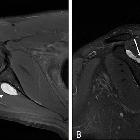

nerve entrapment caused by a large hematoma of the scapula: a case report. Preoperative magnetic resonance image of the lesion A The lesion (line arrow) exhibits high signal intensity on T2-weighted axial imaging. B Sagittal section revealing the heterogenous signal intensity of the cyst (line arrow) with the scapular spine of the right shoulder and infraspinatus muscle (star) denervation

- direct features of entrapment

- swelling, increased size and signal of the nerve

- visualization of the causative factor

- indirect features of entrapment via features of muscle atrophy or acute denervation

- supraspinatus and infraspinatus muscles: compression at the suprascapular notch

- infraspinatus muscle only: compression at the spinoglenoid notch